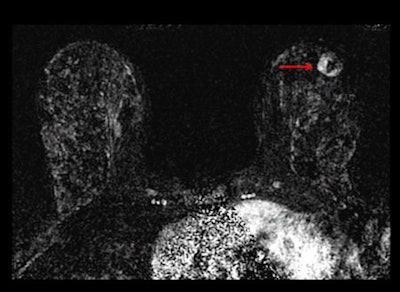

After three years of both mammography and ultrasound screenings, 612 women chose to undergo an MRI scan. As a reference standard, researchers used a combination of biopsy results that showed in situ infiltrating ductal carcinoma, or infiltrating lobular carcinoma in the breast or axillary lymph nodes, and at least a 12-month follow-up.

A total of 16 of 612 women (2.6%) in the MRI substudy were diagnosed with breast cancer. Among the 4,814 screenings in the second and third years combined, 75 women were diagnosed with cancer.

The number of screens needed to detect one cancer was 127 for mammography, 234 for supplemental ultrasound, and 68 for supplemental MRI after negative mammography plus ultrasound screening results.

MRI diagnosed breast cancer in 16 women (3%) from the study group, which translated into a supplemental yield of 14.7 per 1,000. Sensitivity for MRI and mammography plus ultrasound was 100%, specificity was 65%, and positive predictive value of biopsy was 19%.